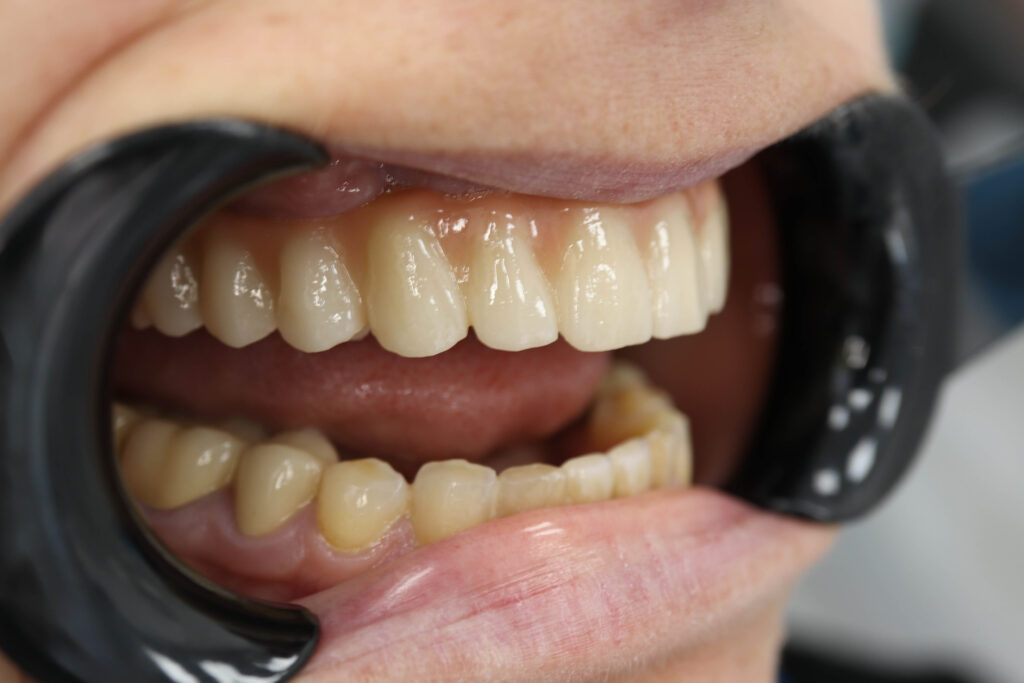

Спустя 25 дней был зафиксирован протез с опопрой на дентальные имплантаты из диоксида циркония.

Результаты